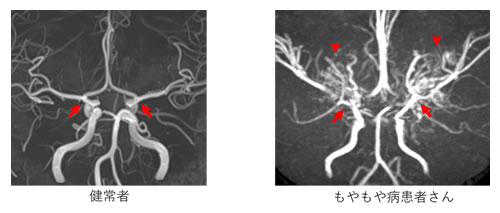

お子さんや若い大人の方で脳の血管が細くなる病気は1950年代からわかっていましたが、「もやもや病」が正式な病名になったのは2003年とごく最近です。脳の太い血管が細くなる一方で、細い異常な血管が「もやもや」とたくさん見えることからこの名前がついています。日本を含むアジアに多い病気で、いまだわからないことも多い病気です。この病気の患者さんは10万人あたり6-10人と言われますが、MRI検査の普及により診断される患者さんが増えています。厚生労働省難病情報センターが公表している一般の方向けの説明も参考になさってください。(https://www.nanbyou.or.jp/entry/47)